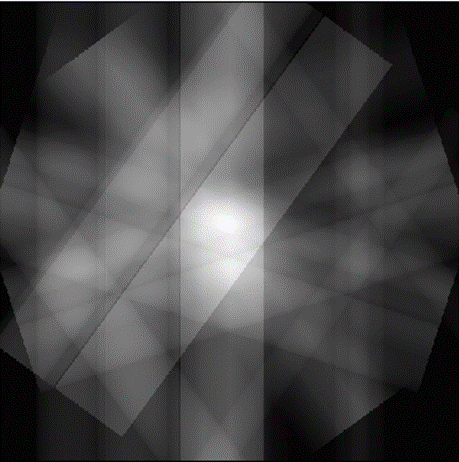

As can be seen in this Figure 2: sinogram of basic image the sinogram is mirror at the 180° mark, however it is mirrored both horizontally and vertically. using this knowledge this means that when taking the back projections of an object, only must take the back projections of the object from 0 to 180 degrees to have enough data to reconstruct the object. To take these back projected and reconstructed the image from them a method must be used called forward projection. This technique takes the slice and angle and project the values at that angle across the image plane, as can be seen in Figure 3.

Figure 3: forward projection of basic image, with 6 projections

Figure 3: forward projection of basic image, with 6 projections